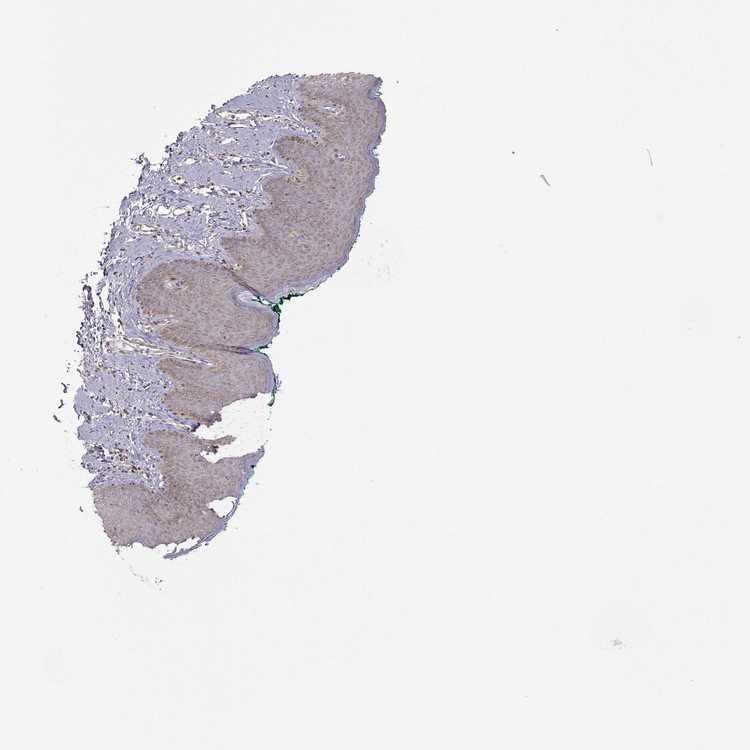

SKIN 1 - Antibody stainingi

Antibody staining in the annotated cell types in the current human tissue is reported as not detected, low, medium, or high, based on conventional immunohistochemistry profiling in selected tissues. This score is based on the combination of the staining intensity and fraction of stained cells.

Each image is clickable and will lead to virtual microscopy that enables deeper exploration of all samples and also displays staining intensity scores, fraction scores and subcellular localization as well as patient and tissue information for each sample.

Antibody HPA049695

Langerhans Not detected

Fibroblasts Low

Keratinocytes Not detected

Melanocytes Not detected